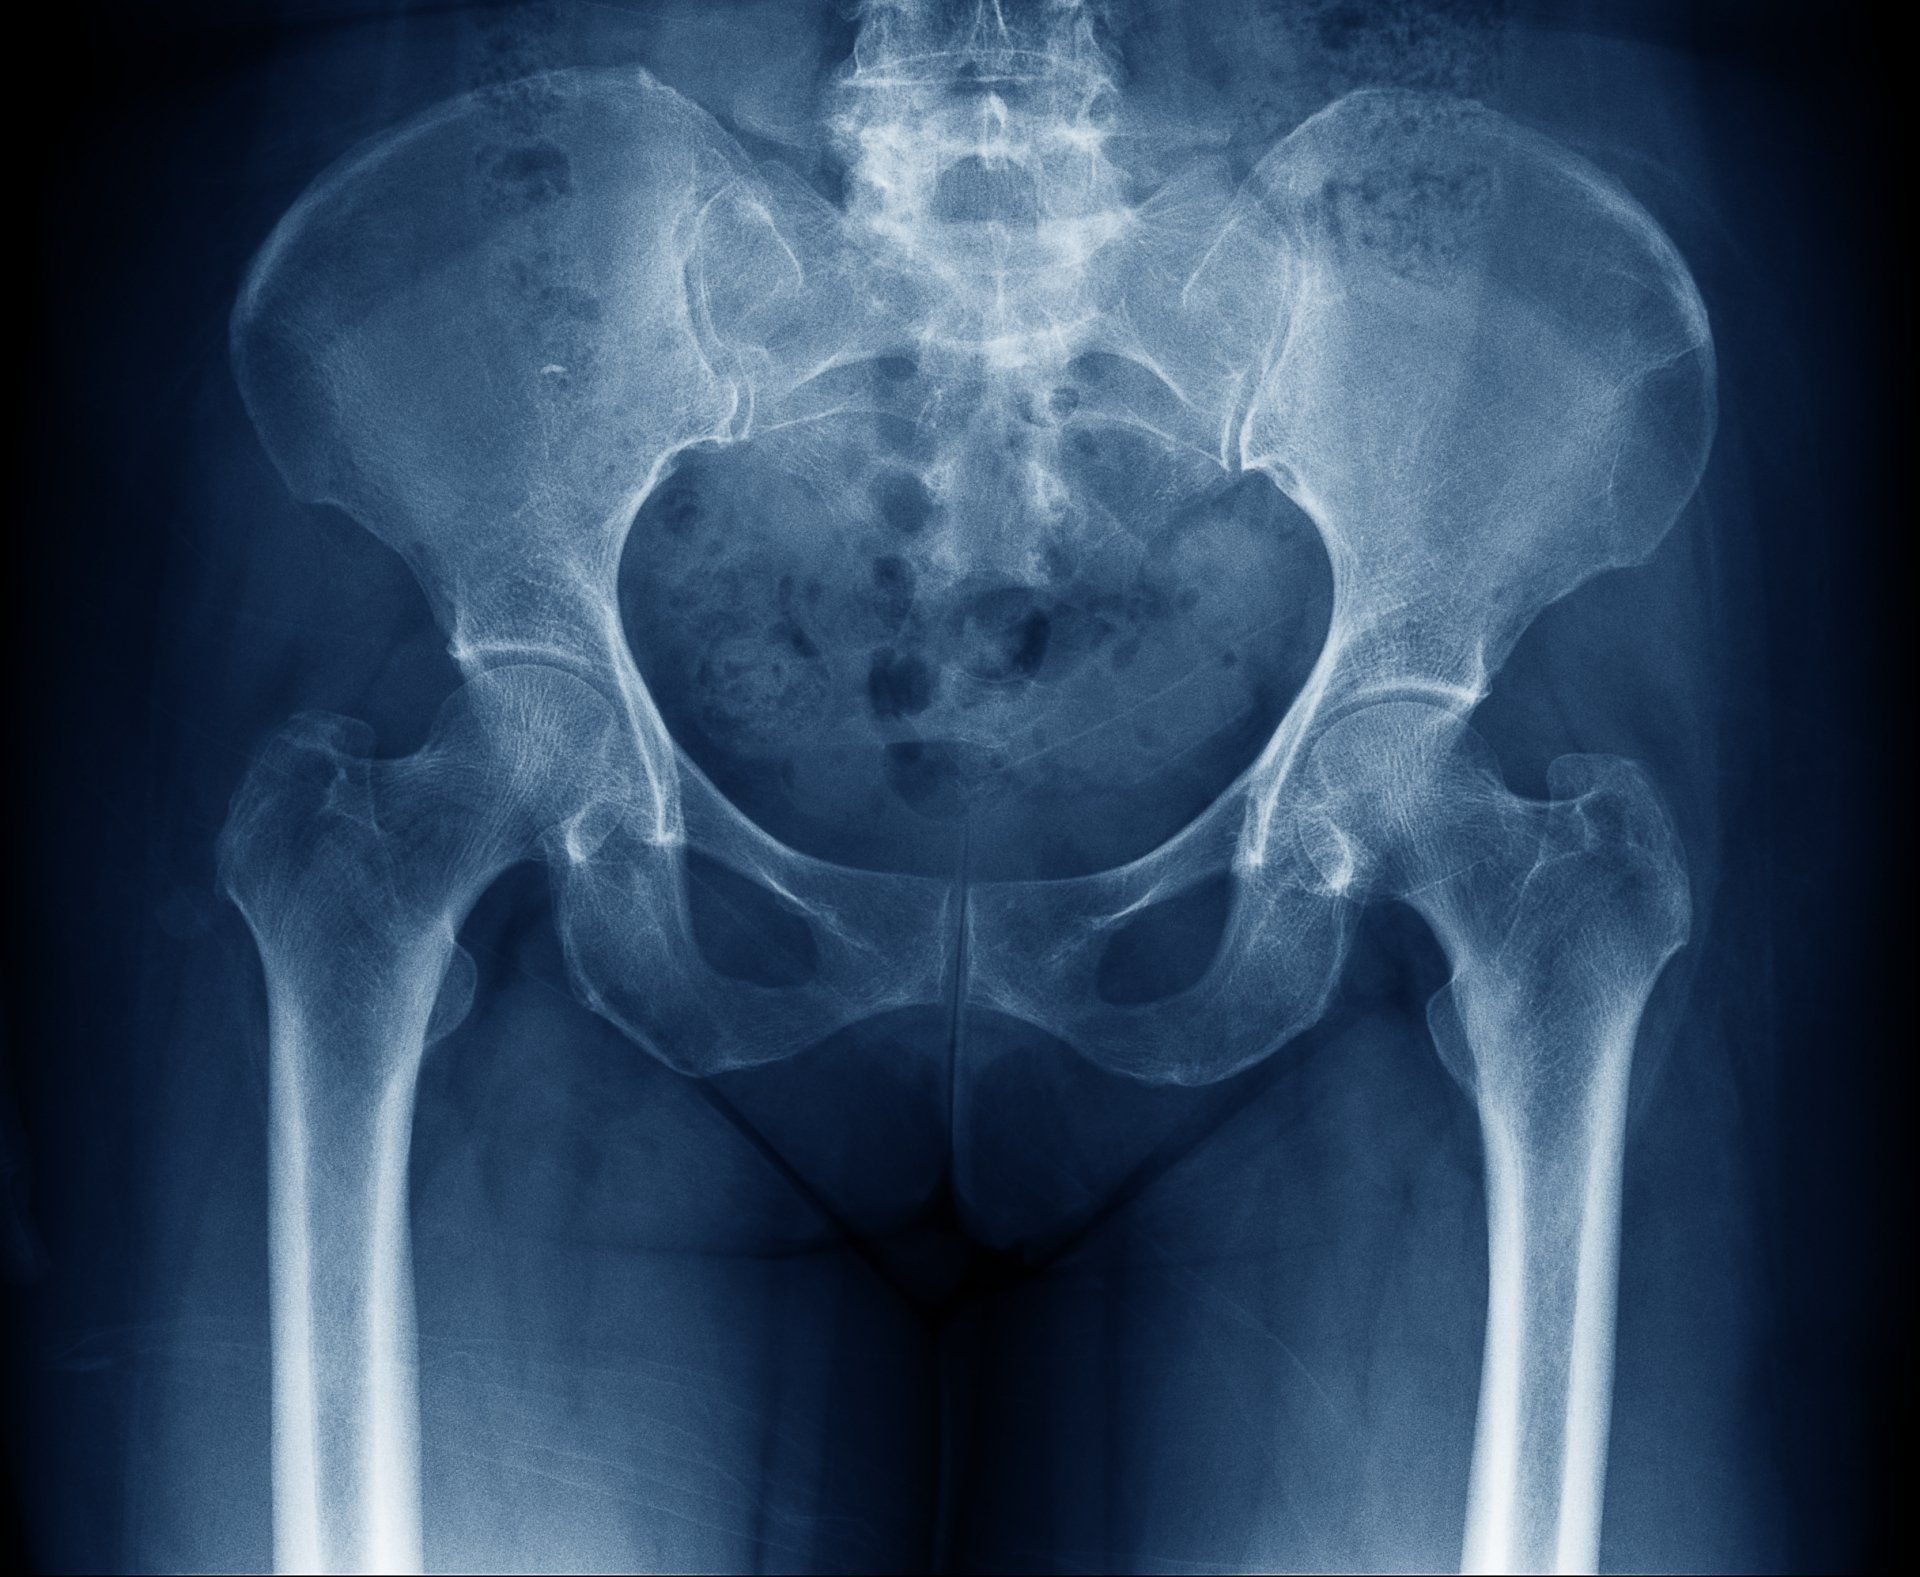

El Dr. López Velázquez es un médico experto y con amplia experiencia en realización de técnicas e infiltraciones ecoguiadas en Madrid Centro. Realiza más de 100 técnicas distintas en todo el cuerpo (hombro, codo, muñeca, dedos, cadera, rodilla, tobillo, pie y también columna).

Las infiltraciones ecoguiadas son necesarias para resolver el dolor de articulaciones profundas como la cadera o de muy pequeño tamaño como la artrosis del pulgar (rizartrosis), por poner algunos ejemplos.